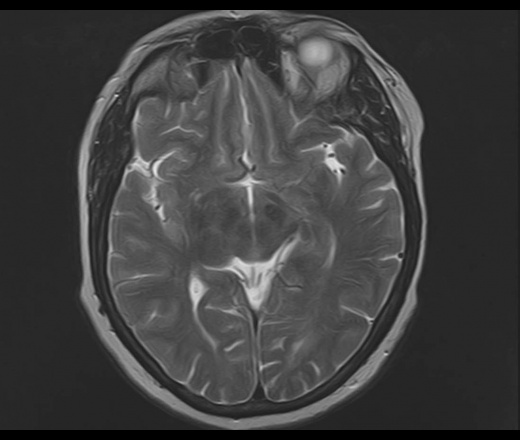

У пациентки 1960 г.р. с 2005 наблюдается птоз, диагноз миастении исключен. МРТ ГМ впервые выполнено в августе 2015 г в плановом порядке, новых жалоб не было, по описанию МРТ - очаговые изменения белого и серого вещества больших полушарий и ствола мозга - признаки энцефаломиелита.

В сентябре 2015 новое МРТ: субкортикальные очаги в белом веществе больших полушарий, не накапливающие контраст; уменьшение размеров ряда очагов - Данных за демиелинизирующее заболевание нет, поствоспалительные изменения. Консультирована в НИИ неврологии, предположено демиелинизирующее заболевание вторичного генеза. В неврологическом статусе: правосторонний птоз, ограничение конвергенции, асимметрия носогубных складок.

Сейчас вновь сделано МРТ, появлись 2 новых очага: в полюсе правой височной доли и поперечной височной извилине слева. Очаг в задних отделах левой теменной доли (угловая извилина) увеличился в размерах. С контрастом пока не работаем.

Подскажите, пожалуйста, что это за процесс? Поражено только белое вещество или серое также? Есть ли поражение ствола мозга?

Действительно, динамика отрицательная и на первичную демиелинизацию не тянет. Какой-то продолжающийся энцефалит, какой именно и гадать нечего, это не наше дело, навскидку можно написать длинный ряд типа Эбштейна-Барра и пр, всё требует серологического доказательства.. В стволе ничего не увидел. Поражено белое и серое вещество.